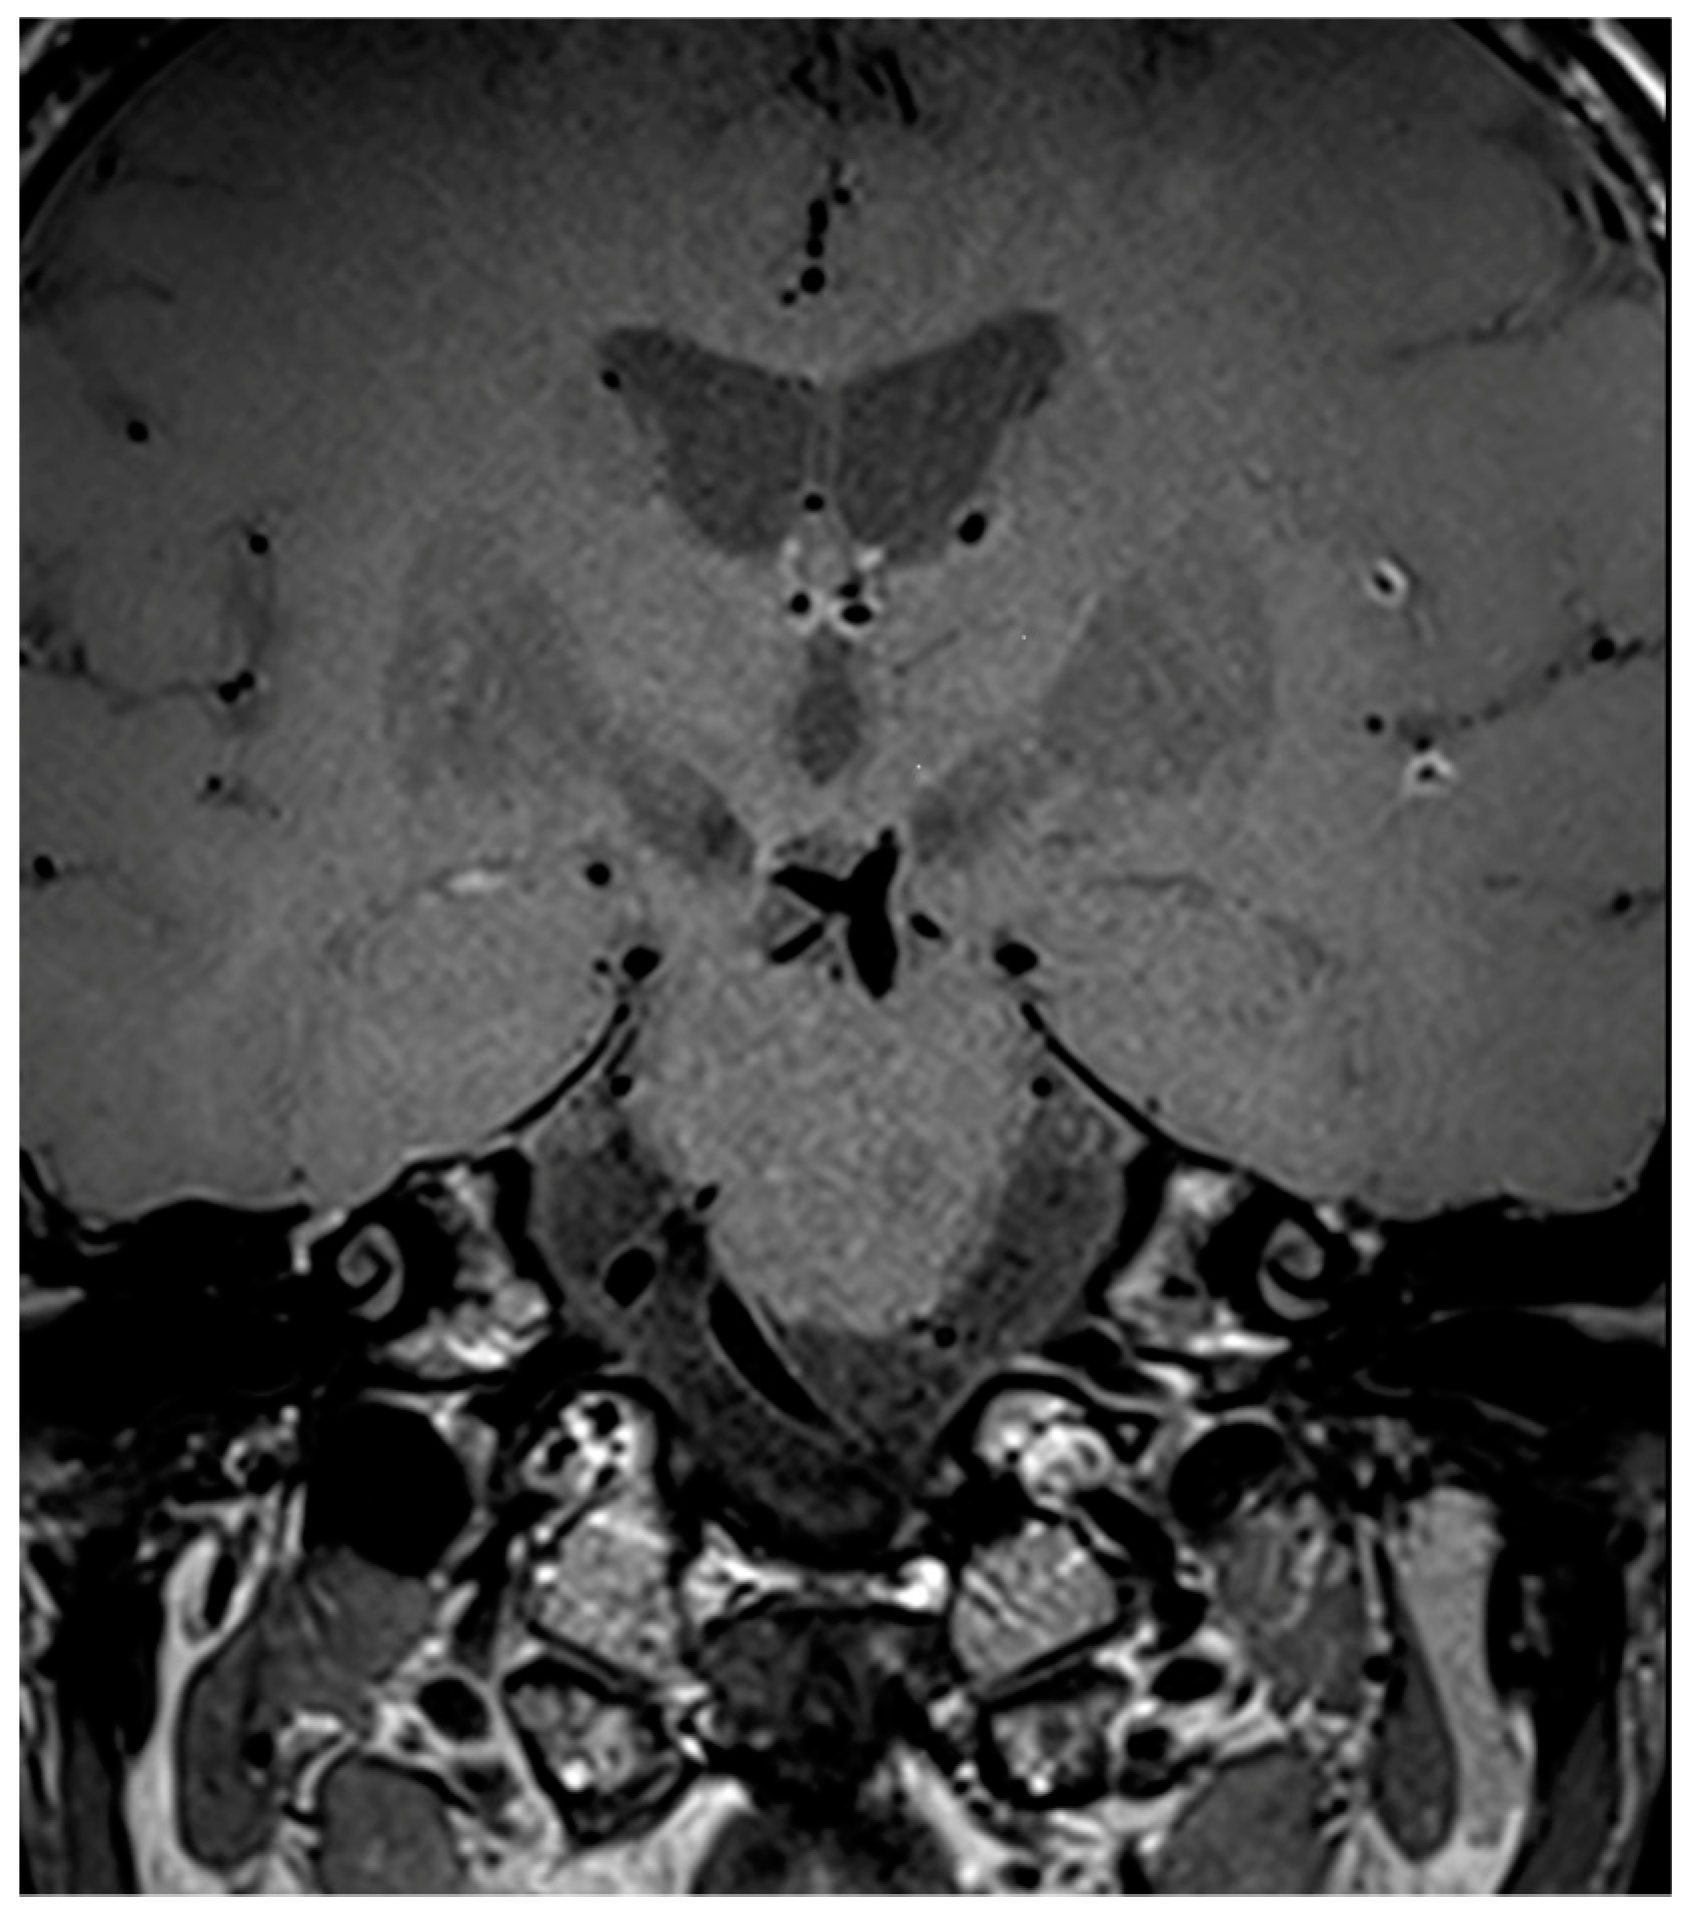

| 66Y, M | 3 | Present | Present | Bilateral Basal Ganglia, Left SCA | SCA | ACM (M1) ICA BA | Present | Subtentorial |

| 32Y, F | 1 | Absent | Absent | No | None | None | Absent | // |

| 49Y, M | // | Absent | Absent | No | ACM (M2) | ACM (M2) | Present | Supratentorial |

| 83Y, F | 2 | Present | Present | Cortical-Subcortical in PCA Territory | PCA (P2) | None | Absent | // |